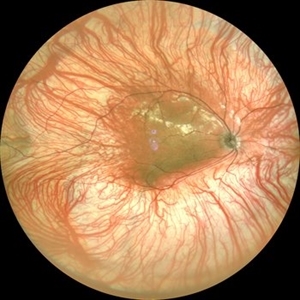

Familial Exudative Vitreo-retinopathy

Jul 6 2021 by Akansha Sharma

Color photo montage of 21-year-old male with familial exudative vitreoretinopathy in an amblyopic eye.

Photographer: Dr. Akansha Sharma-Retina Foundation, Ahmedabad

Condition/keywords: familial exudative vitreoretinopathy (FEVR), retinal ischemia